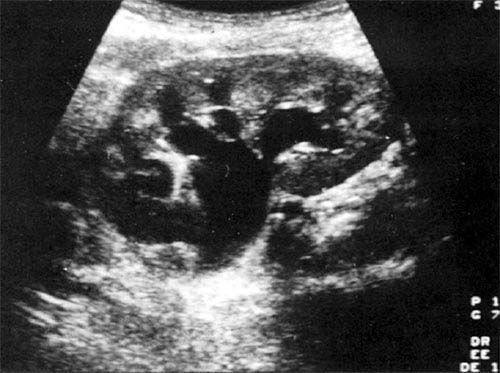

Hydronephrosis

Hydronephrosis.

echo hypodense

area

Kidney